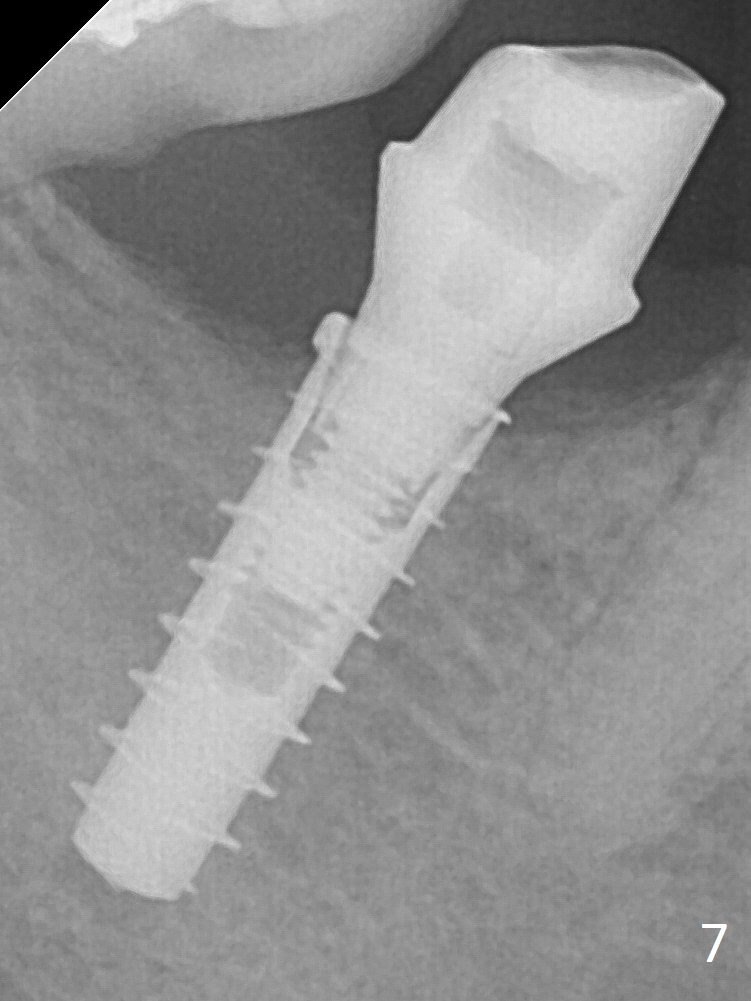

There is no apparent bone loss 4 months postop (Fig.7), related to the advantage of the narrow implant (less traumatic).